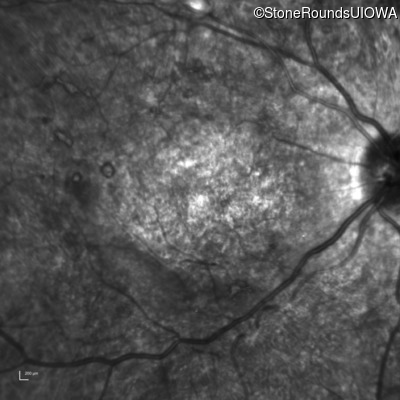

Infrared Fundus Photograph - Right - 20/400 sc

Exemplar